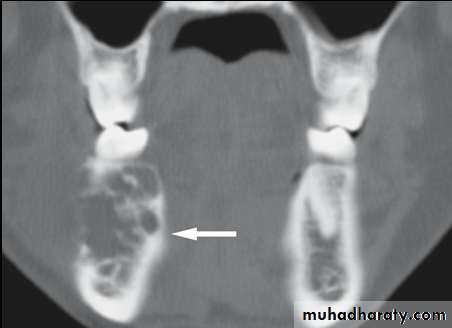

• Radiography:• Typically appears as multi locular radiolucent area with well defined scalloped margin or soap bubble.

• Copyright 2003, Elsevier Science (USA). All rights reserved.